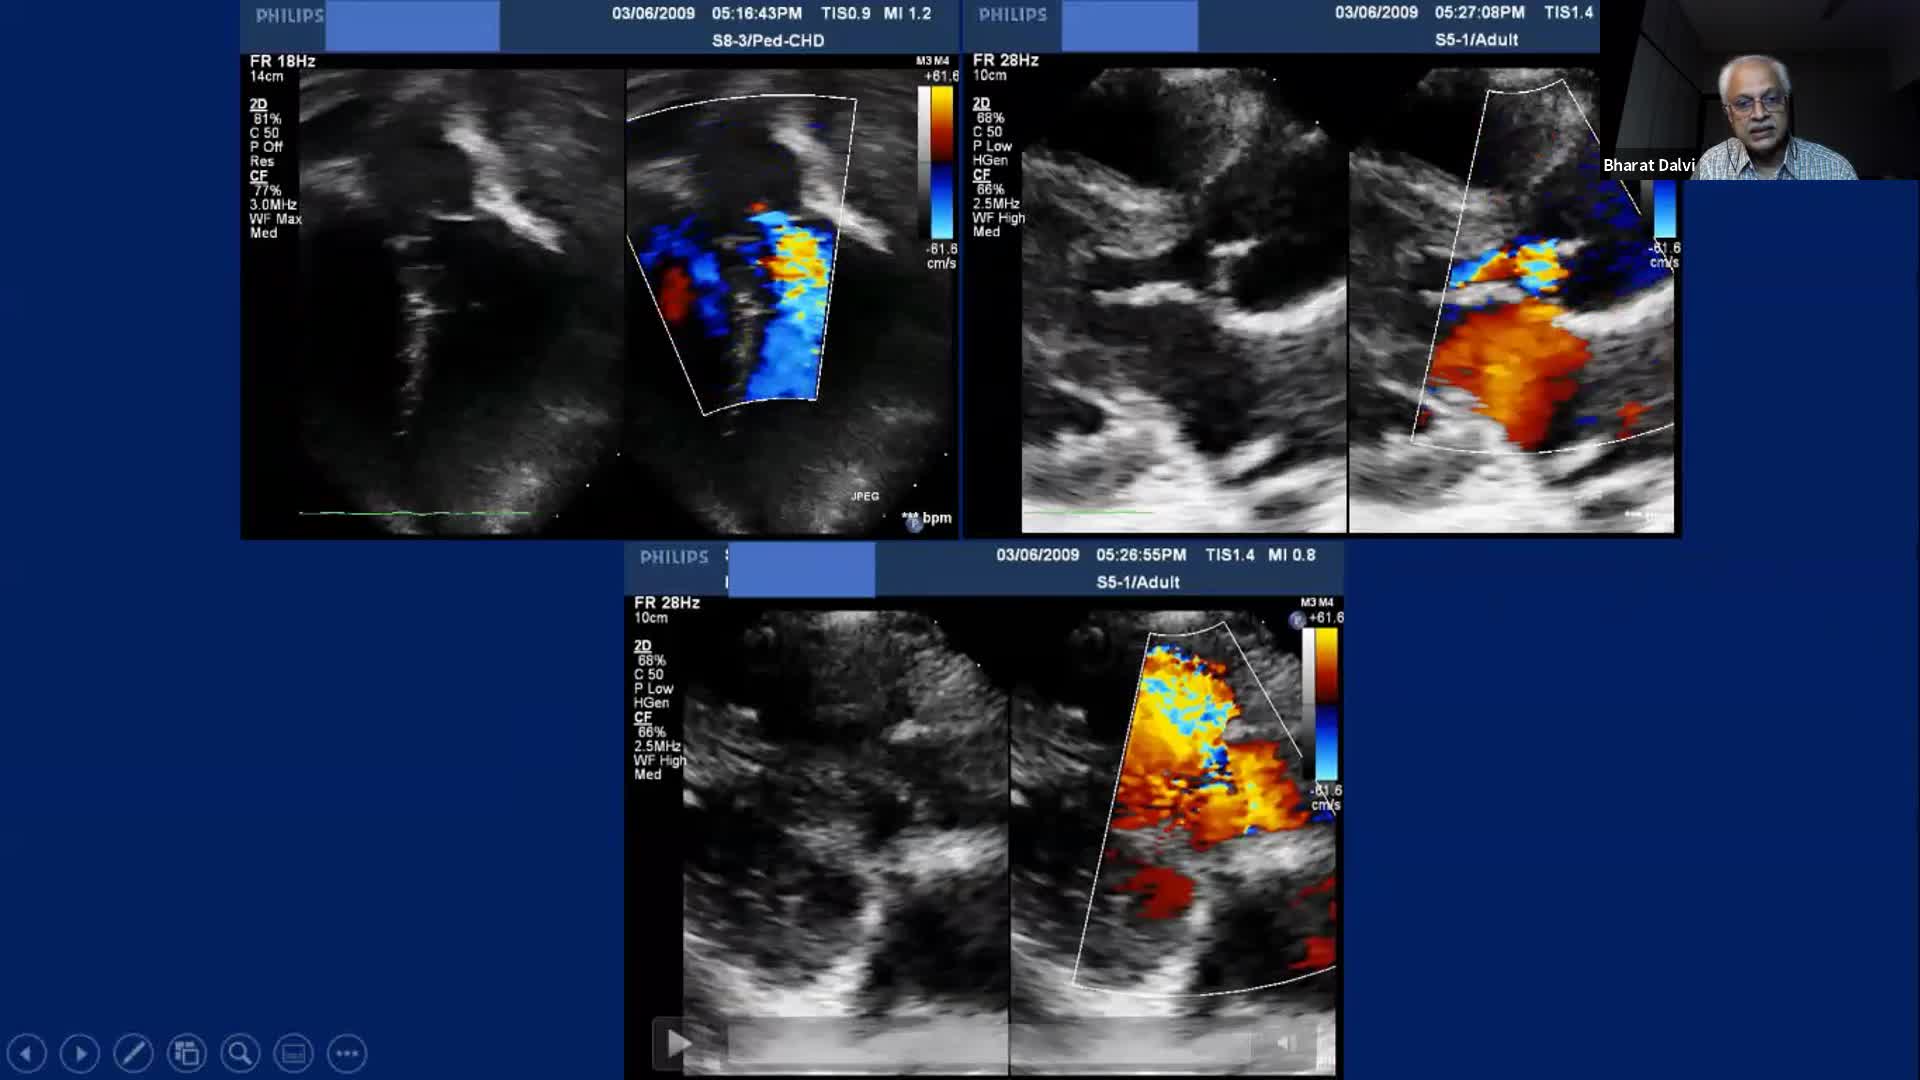

CSI CATHLAB LIVE - INTER-ATRIAL SHUNT FOR DECOMPRESSION OF THE LEFT ATRIUM IN A PATIENT WITH VERY SEVERE HEART FAILURE WITH THE AFR DEVICE